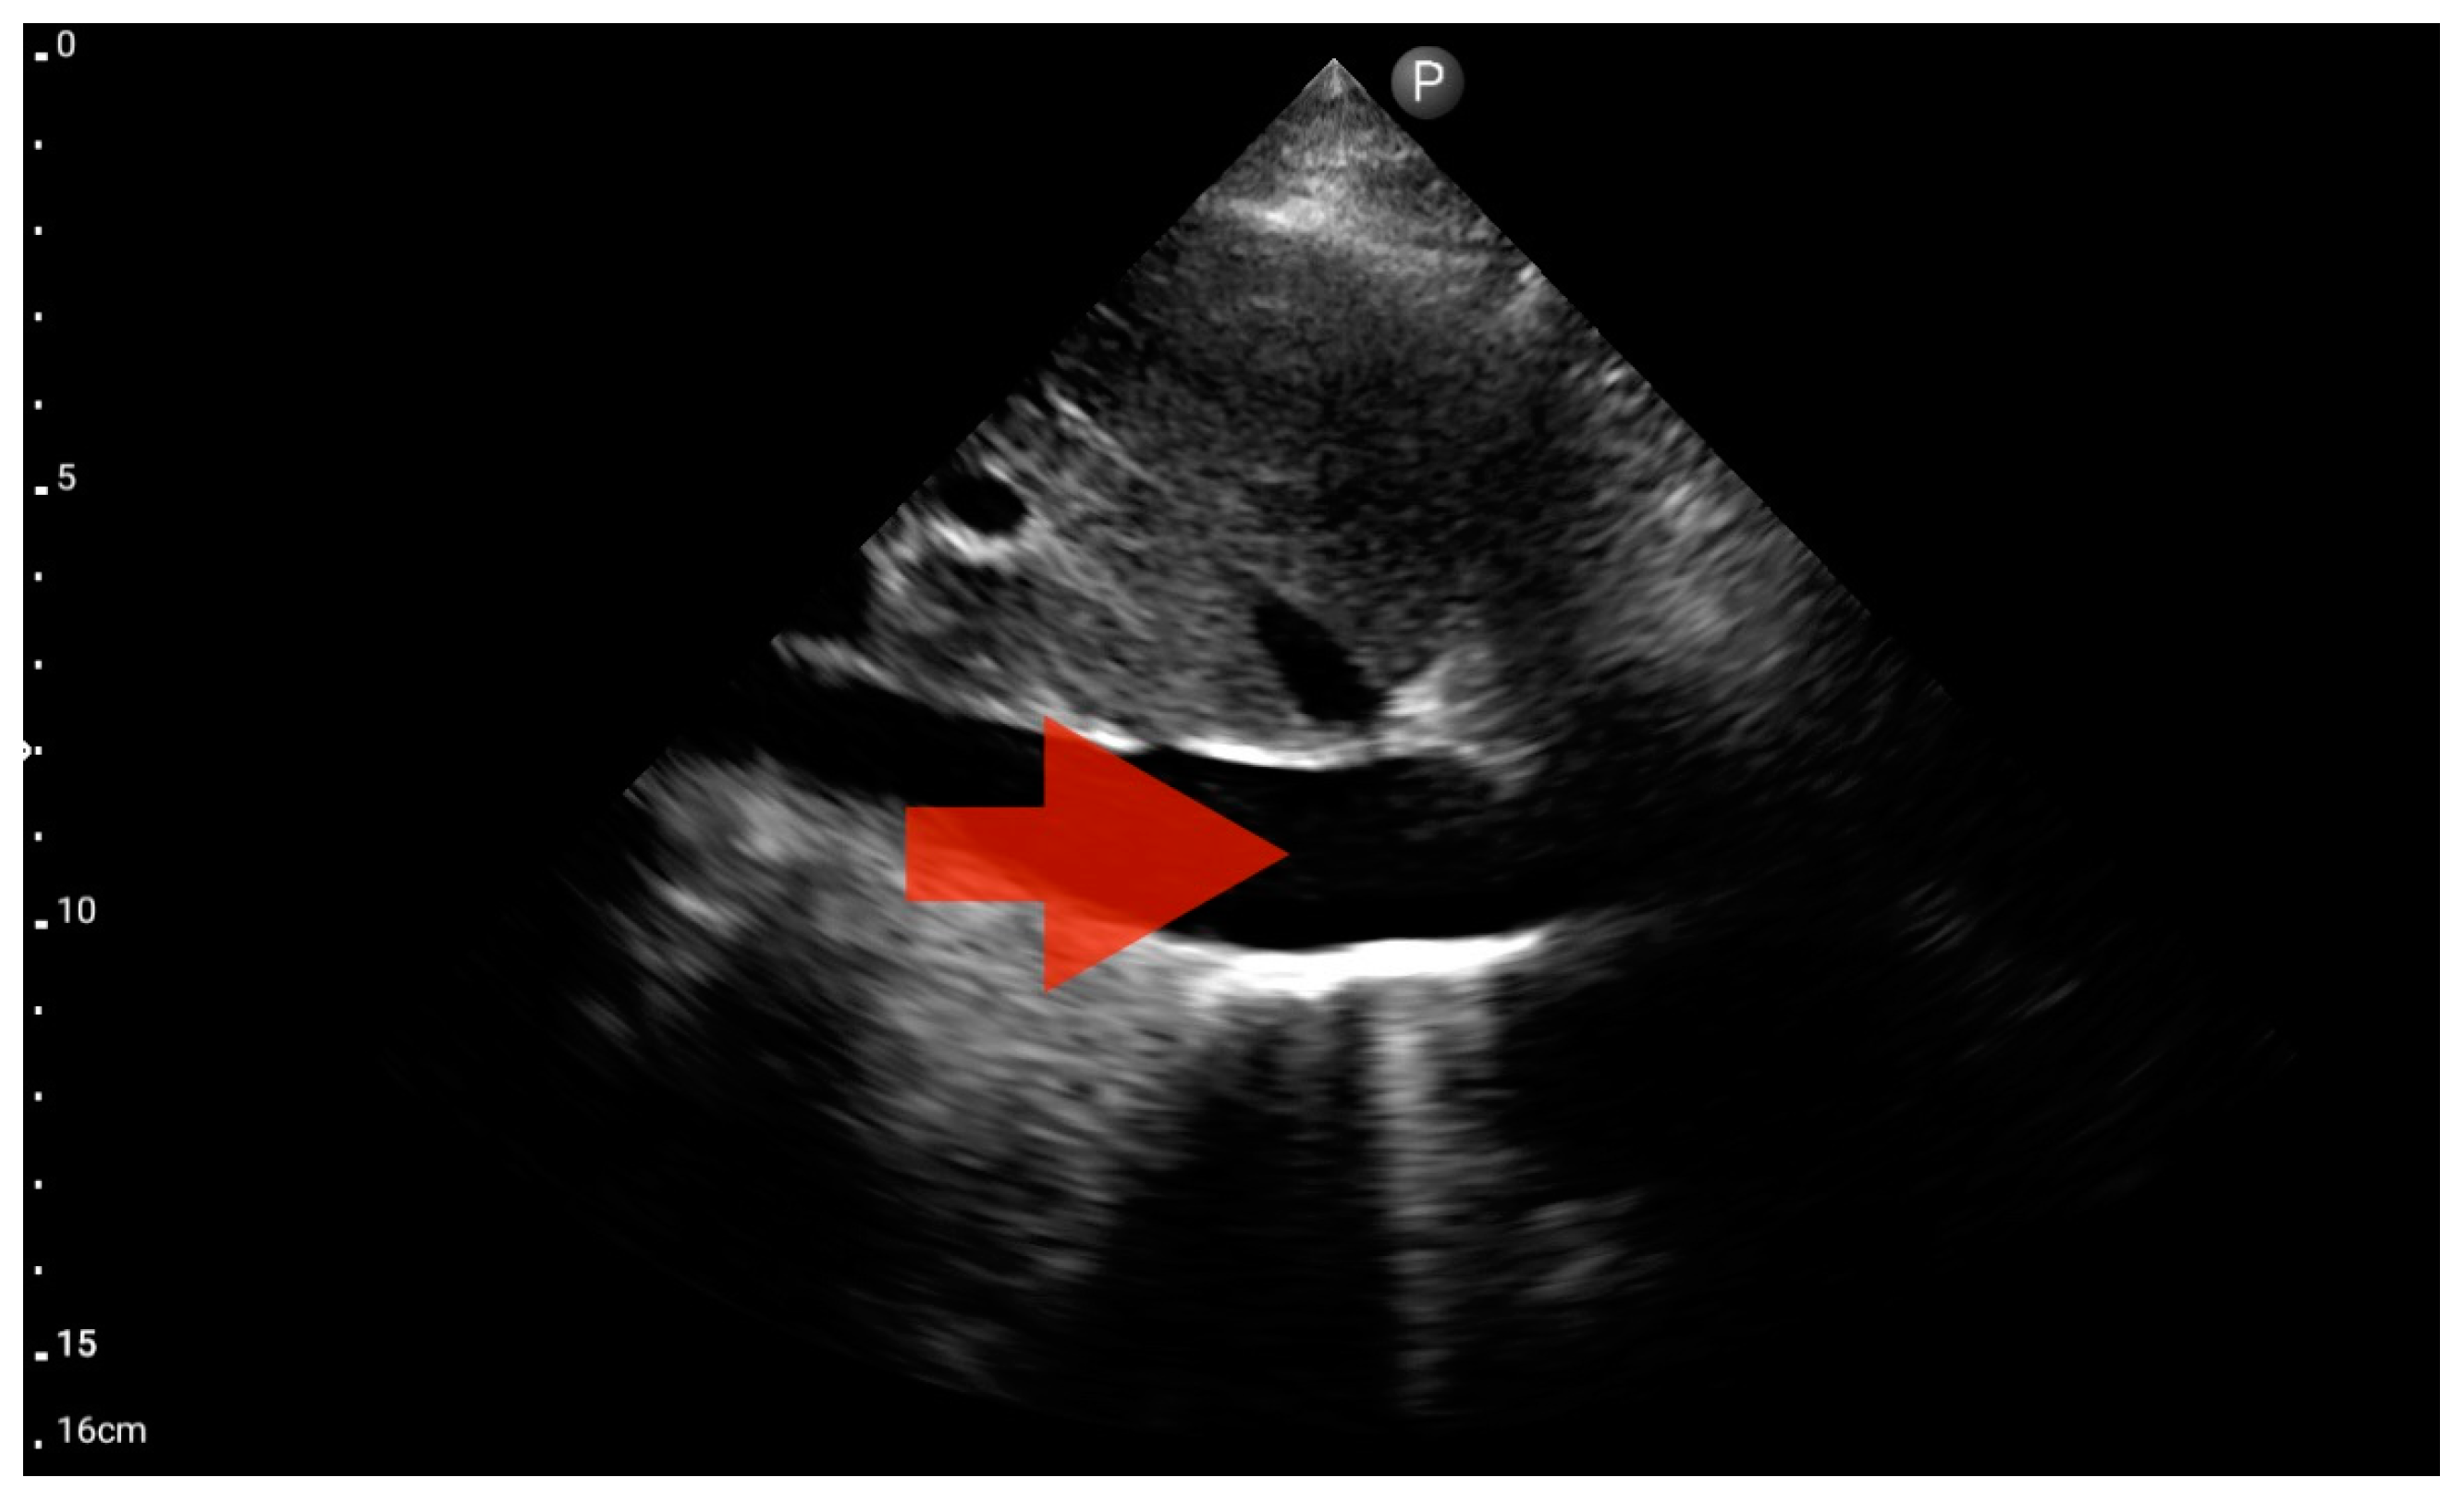

Figure 14.

Pericardial effusion; position: apical four-chamber (FATE protocol). Sector probe; the red arrow indicates free fluid in the pericardium, which did not cause a sonographic image of cardiac tamponade (source: author’s material—DK).